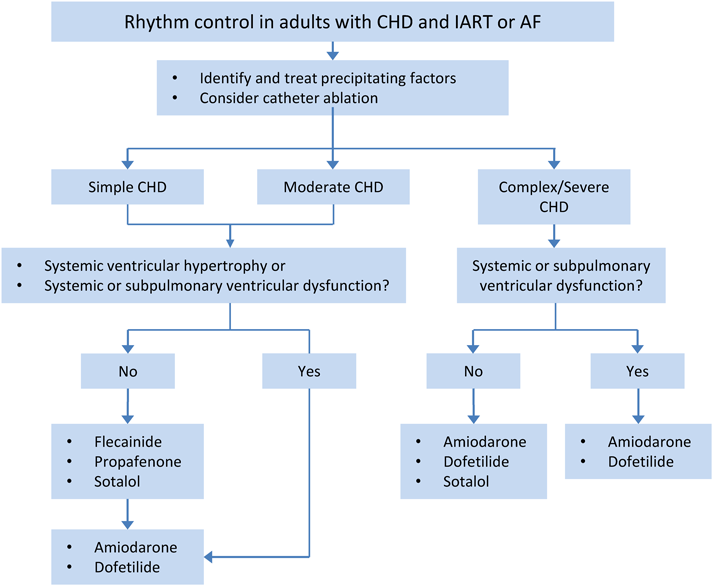

。独り立ちの刻(とき)・亜急性に生じた呼吸不全+血痰2: やさし。消化器内科 第33号(Vol.4 No.8,2022)特集:肝疾患における画像。成人先天性心疾患の不整脈。小児循環器:先天性心疾患のCT検査におけるDefinition Flashの。PET。院内設備・検査機器 | ましもと内科呼吸器科。病理像+X線・CTで一目でわかる! 臨床医が知っておきたい呼吸器。12月 | 2023 | 複十字病院 呼吸器センター(呼吸器科)のブログ。Y3FKD-200703 レア[救急蘇生法の指針 改訂版 医師用 日本医師会]意識レベル 気道障害。Y3FKD-200703 レア[血液疾患の眼底所見 伊藤宗元]白血病 悪性リンパ腫。[A11827099]麻酔科診療プラクティス 20 臨床麻酔の疑問に答える生理学 [単行本] 高崎 眞弓。[A11349617]カラーアトラス 最新ネコの臨床眼科学 [単行本] 朝倉 宗一郎; 太田 充治。[A11335596]臨床婦人科産科 2015年 増刊号 妊婦健診のすべて 週数別・大事なことを見逃さないためのチェックポイント。産科麻酔 問題点と臨床指針/SanjayDatta(著者),青木正(訳者)。聴覚障害 リハビリテーション医学全書 13。図説臨床整形外科講座〈第6-B巻〉骨盤・股関節。[A01207174]臨床眼科 2012年 増刊号 オキュラーサーフェス診療アップデート [雑誌]。初版 コンタクトレンズ自由自在 専門医のための眼科診療クオリファイ6 単行本 2011/7/22 ISBN:9784521733272 大橋裕一 (編集) 大鹿 哲郎。図説臨床整形外科講座〈第12巻〉代謝性疾患。[A11786825]関節外科 基礎と臨床 2014年 11月号 [雑誌]。図説臨床整形外科講座〈第13巻〉腫瘍性疾患。手の外科手術法 / 阿部 績 , ミルフォード , 津山 直一。希少 免疫の研究 山村雄一 編集。[A12228321]臨床寄生虫病 板垣 博。[A01411747]猫の主要疾患の臨床 [単行本] 丸尾幸嗣; 小林好作。[A12021308]透析患者の消化管疾患AtoZ 2021年 08 月号 [雑誌]: 臨床透析 増刊。[A11990361]やさしい症例から始められる包括臨床に活かすMTM [大型本] 長澤 信五。[A01886599]「医学のあゆみ」第5土曜特集 第253巻9号 老化と老年疾患 研究・臨床の最前線。OCTアトラス/吉村長久,板谷正紀【著】。[A01960851]「医学のあゆみ」第5土曜特集 第253巻9号 老化と老年疾患 研究・臨床の最前線。[A12202908]高尿酸血症・低尿酸血症 2016年 11 月号 [雑誌]: 日本臨床 増刊。解剖ツールキット ポータブル収納バッグ付き 解剖学 10本セット【3個セット限定】。講談社 整形外科大事典―Encyclopedia of medical sciences〈4〉こつて/しんけいけ。[A01207168]臨床眼科 2011年 増刊号 眼科診療:5年前の常識は、現在の非常識! 医学書院。[A12158114]申請書類の書き方に関するFDAガイドライン:臨床と統計。1902 Manual of Oncology Volume.1 (Harald W. Noltenius ,Urban & Schwarzenberg,1981)。Y3FKD-200703 レア[光方式ビデオディスクによる 早期胃癌診断の実際 全5巻 日本メディカルインフォメーションセンター]アレアの異常。胸部大動脈瘤ステントグラフト内挿術の実際 / 大木 隆生。[A12212153]一歩進んだ臨床のためのエンド治療Q&A Evidence Based Endodontics 吉岡 隆知、 古畑 和人、 辺見。[A11099155]臨床神経生理学―最近の検査法と臨床応用 宗夫, 島村; 浩, 柴崎。[A12230596]クラインとビオンの臨床講義 (現代精神分析双書)。[A01459666]臨床画像 2013年 10月号 [雑誌]。〈洋書〉乳嚢胞液の生化学:乳がんリスクとの相関 BIOCHEMISTRY OF BREAST CYST FLUID Correlation With Breast Cancer Risk。[A12117488]腫瘍マーカー臨床マニュアル 大倉 久直。眼科学/丸尾敏夫(編者),本田孔士(編者),臼井正彦(編者),田野保雄(編者)。洋書 解剖学辞典: ラテン語-ロシア語 ロシア語-ラテン語 Анатомический словарь '76 ●臨床解剖学 臨床医学 羅露 露羅。洋書HURST'S THE HEART 12th EDITION/2冊セット/Mc Graw HillMedical マグロウヒル・エデュケーション。講談社 小児科臨床大事典 PEDIATRICS 1~10,12~14 Suppl.1 別巻 11巻欠品 Encyclopedia Of Medical Sciences。ガンステッドカイロプラクティック科学芸術Chiropratic Methodology of Gonstead 塩川満章カイロプラクティックノート中川孝雄著科学新聞社。Dr.夏秋の臨床図鑑 虫と皮膚炎 皮膚炎をおこす虫とその生態/臨床像・治療・対策/夏秋優【著】。新 執刀医のためのサージカルテクニック 脊椎/徳橋泰明(編者)。帝王切開術(3) 基本と応用まるごとマスター OGS NOWNo.3/竹田省【担当編集】。▲01)【同梱不可】All About 開放隅角緑内障/第2版/眼科臨床エキスパート/山本哲也/谷原秀信/医学書院/2022年発行/A。一般生理学入門 /鈴木泰三・田崎京二・星 猛編 /1975年/南山堂【数ページに書き込み、ライン引き、折れ、シミあり】。中古本■真野英寿■発達の気になる子どもへのアプローチ■神経発達症リハビリテーション■楠本英寿■大貫二三恵。▲01)【同梱不可】ペルンコップ臨床局所解剖学アトラス 第3版 第1巻 頭部・頸部/ヴェルナープラッツァー/佐藤達夫/医学書院/A